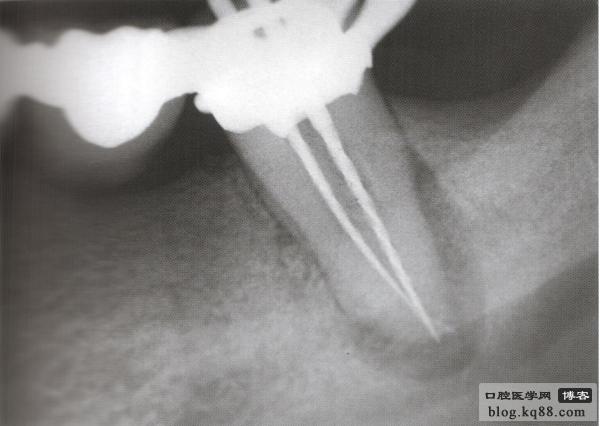

病例2 修復(fù)后根尖出現(xiàn)炎癥冠上開孔再治療

修復(fù)后出現(xiàn)根尖周炎 去除原根充物后試主尖